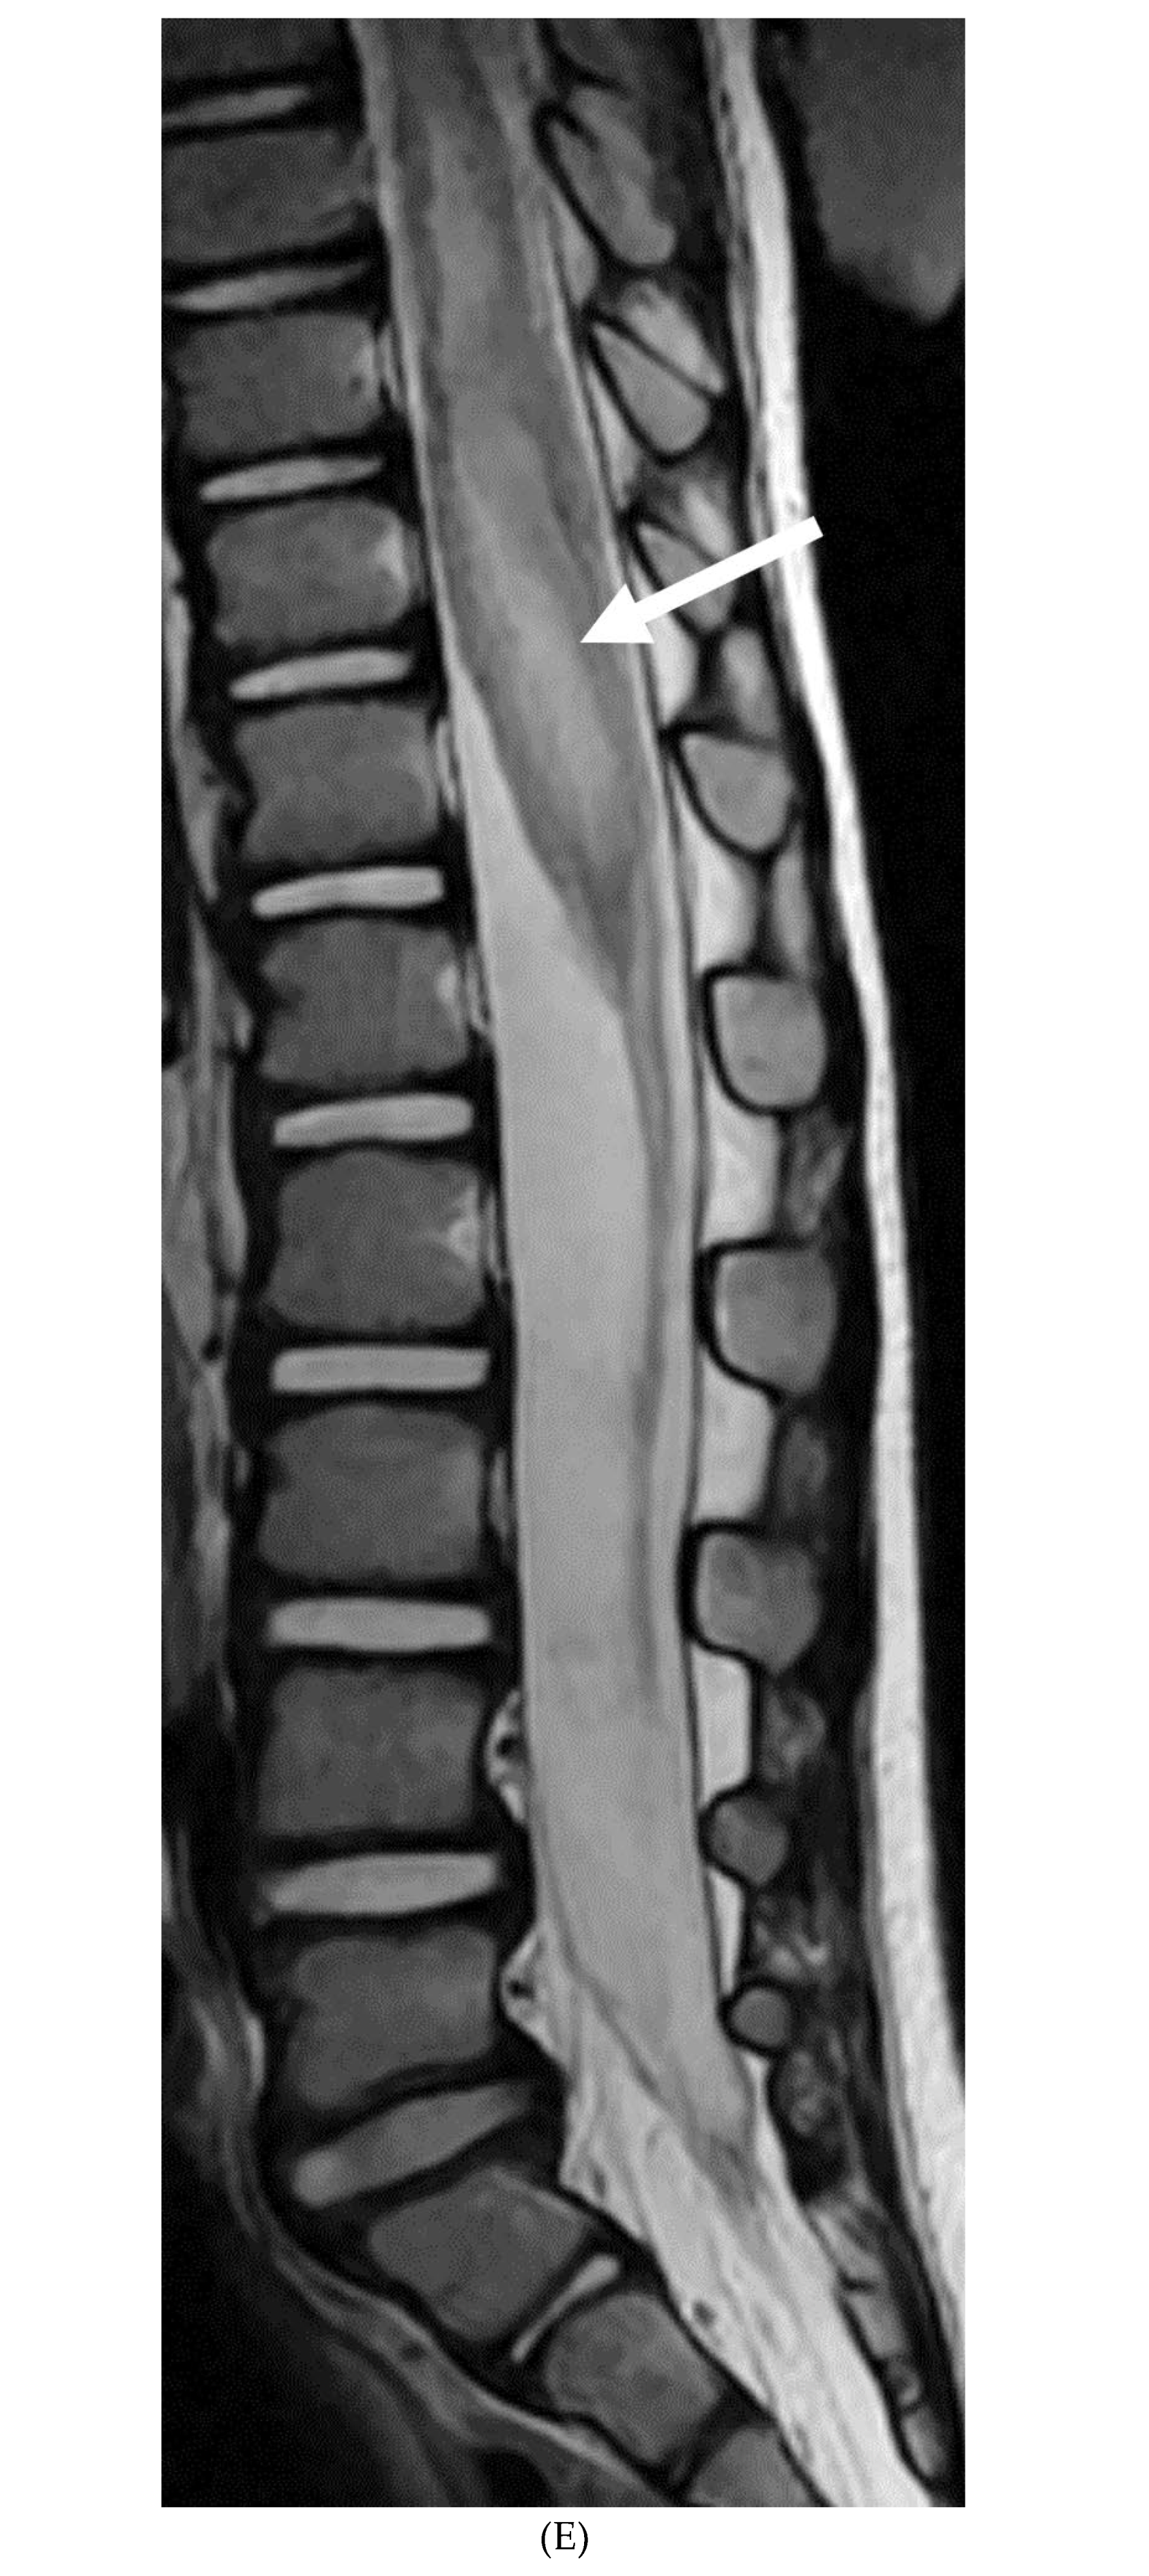

INTRACRANIAL HYPOTENSION (IH)

- Peterson EE, Riley BL, Windsor RB. Pediatric Intracranial Hypotension and Post-Dural Puncture Headache. Semin Pediatr Neurol. 2021 Dec;40:100927. Epub 2021 Sep 3. PMID: 34749914. [CrossRef]

- Schievink WI, Maya MM, Louy C, Moser FG, Sloninsky L. Spontaneous intracranial hypotension in childhood and adolescence. J Pediatr. 2013 Aug;163(2):504-10. Epub 2013 Feb 28. PMID: 23453548. [CrossRef]

- Shah LM, McLean LA, Heilbrun ME, Salzman KL. Intracranial hypotension: improved MRI detection with diagnostic intracranial angles. AJR Am J Roentgenol. 2013 Feb;200(2):400-7. PMID: 23345364. [CrossRef]

- Yuh EL, Dillon WP. Intracranial hypotension and intracranial hypertension. Neuroimaging Clin N Am. 2010 Nov;20(4):597-617. PMID: 20974378. [CrossRef]

- Medina JH, Abrams K, Falcone S, Bhatia RG. Spinal imaging findings in spontaneous intracranial hypotension. AJR Am J Roentgenol. 2010 Aug;195(2):459-64. PMID: 20651205. [CrossRef]